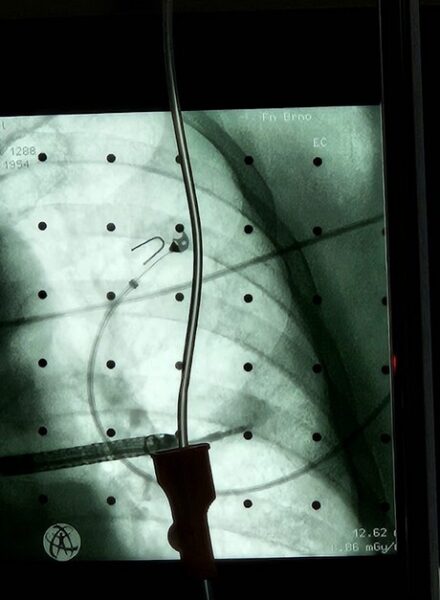

Pokud CT zachytí podezřelé ložisko, následuje bronchoskopie – vyšetření dýchacích cest pomocí tenkého nástroje s miniaturní kamerou. Lékaři využívají stále sofistikovanější navigační systémy s umělou inteligencí, které kombinují snímky CT a magnetické rezonance a vytvářejí 3D model dýchacích cest.

„Díky tomu dokážeme přesně naplánovat cestu bronchoskopu k nádoru a odebrat vzorky hned napoprvé – bez nutnosti opakování, které by prodlužovalo cestu pacienta k zahájení léčby,“ vysvětluje profesor Sova. Umělá inteligence navíc umí s vysokou spolehlivostí rozpoznat i normální nálezy – pokud označí snímky ze zobrazovacích metod za fyziologické, s velkou pravděpodobností je nález skutečně neškodný.